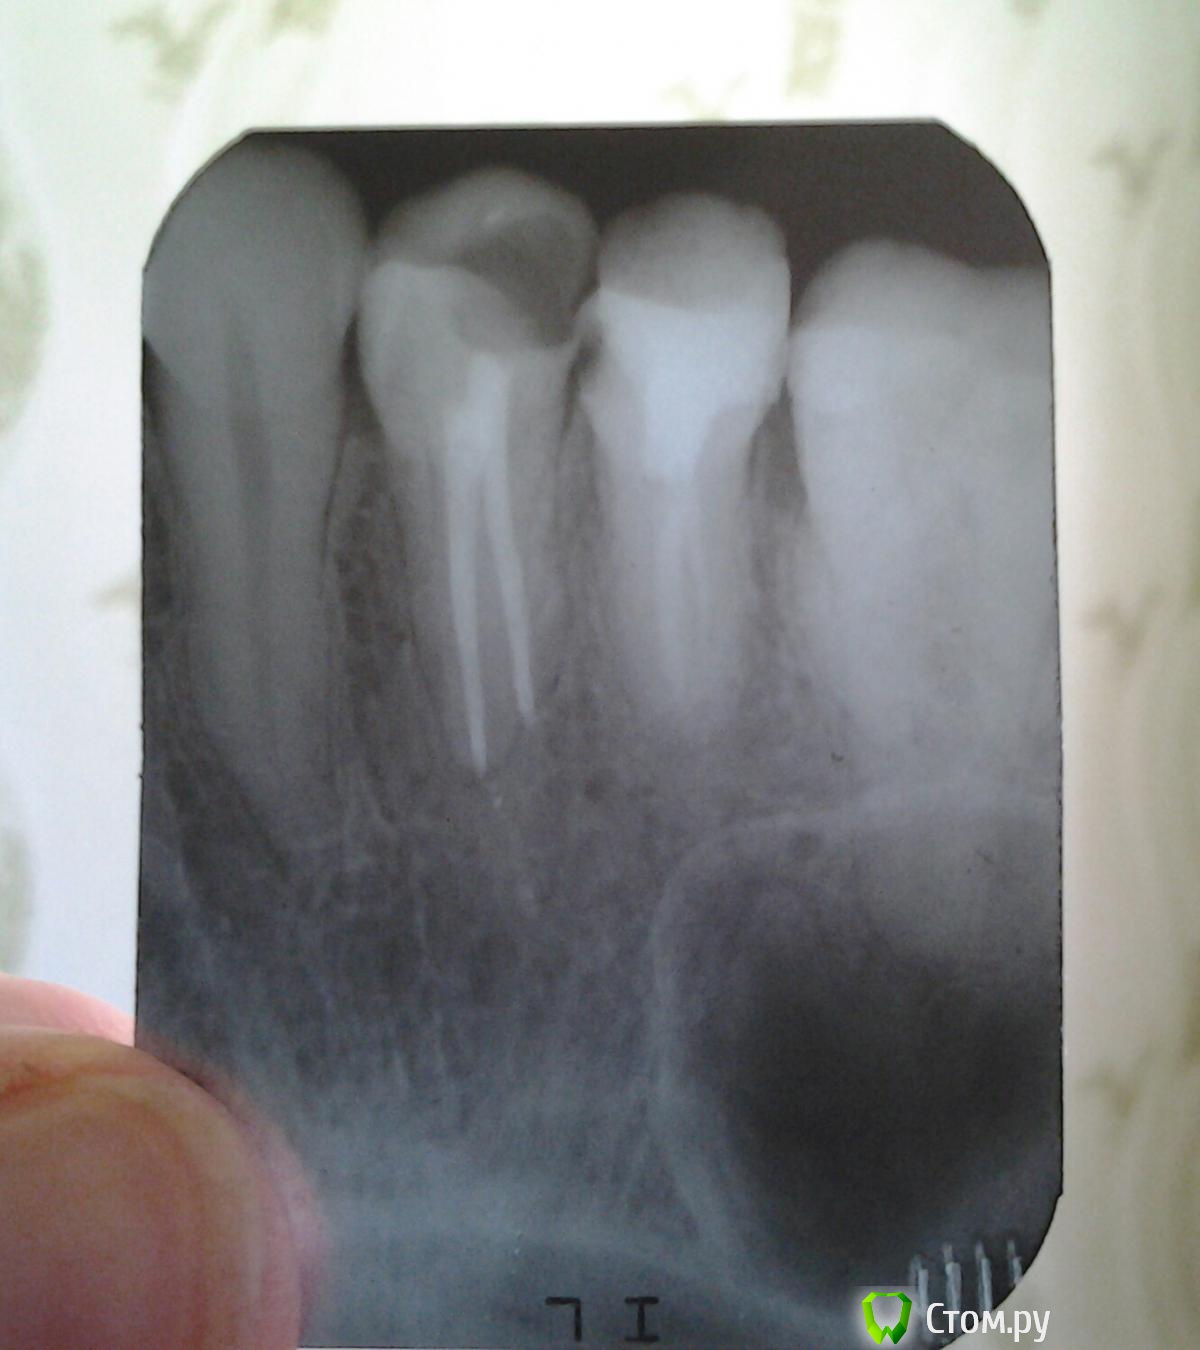

Икс Опубликовано 22 августа, 2014 Поделиться Опубликовано 22 августа, 2014 (изменено) Здравствуйте. Долго лечила невралгию,оказалось пульпит. То есть запустила пульпит. Вылечила его ( 4-ка справа сверху), запломбировали каналы и зуб. В первые дни после лечения боль при накусывании была невероятная, вплоть до подпрыгивания при соприкосновении с вылеченным зубом. Потом боль пошла на спад. Прошло уже 2 месяца, а до конца не прошло. Боли нет, но есть неприятная чувствительность корня зуба (или десны в районе корня) при надавливании, еще ощущение, что внутри зуб слегка распирает и дискомфорт при постукивании по зубу ногтем (но не боль). Снимок новый (после лечения спустя 2 месяца) на снимке леченный зуб второй слева. Что это может быть? Почему так чувствительно у корня зуба? Изменено 22 августа, 2014 пользователем Икс Ссылка на комментарий

Гарриевич Опубликовано 23 августа, 2014 Поделиться Опубликовано 23 августа, 2014 По снимку все в порядке. Пломба на зубе сейчас стоит постоянная? 1 Ссылка на комментарий

red_butler Опубликовано 23 августа, 2014 Поделиться Опубликовано 23 августа, 2014 По снимку все в порядке. + 1, хорошо бы Кт сделать и перелечить соседний зуб 1 Ссылка на комментарий

red_butler Опубликовано 23 августа, 2014 Поделиться Опубликовано 23 августа, 2014 Да, пломба стоит уже постоянная. Такая чувствительность у корня, насколько я помню была еще до лечения пульпита, поэтому я и думала тогда, что невралгия. Мой стоматолог тоже по снимку сказала, что все нормально. Предположила, что из-за десны между леченным зубом и соседним. В соседнем (уже давно без нерва), который вы упомянули, чтобы перелечить, была ступенька под которую постоянно забивалась пища. Видимо из-за этого и развился пульпит. Сейчас врач убрала на нем пломбу и убрала эту ступеньку, оставив десну открытой, пломбу поставит позже. Велела полоскать десну. Я полощу уже почти неделю. А неприятные ощущения так и есть. Поэтому хочу проконсультироваться. Неужели из-за десны может быть неприятная чувствительность аж у корня зуба?сейчас что пломбы вообще нет? Второй премоляр требует повторного лечения каналов. Оба зуба нужно протезировать коронками, а не пломбы менять. Боль может быть, если нарушен протокол изоляции и механической-медикаментозной обработки корневых каналов. Сделайте Кт Ссылка на комментарий